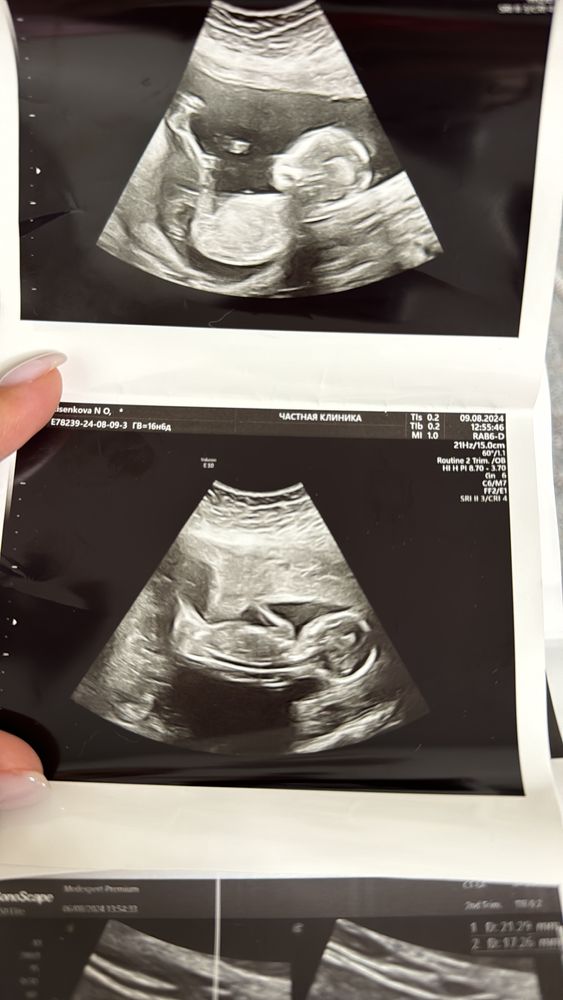

Всем привет. Такая ситуация, ходила в 16,3 недель на узи специально узнать пол ребенка, врач уверенно сказал мальчик, показал 3 раза мне все, и в заключении написал плод мужского пола. Я решила для достоверности пойти к другому через 3 дня, в 16,6 получается. Врач говорит никакого мальчика, тут девочка. Я ей говорю что вот мальчик был, она мне ответила что у нее 20 лет стажа , но на экране не выводила мне гениталии, поэтому я засомневалась. Первое фото типа девочка, второе типа-мальчик

Маргарита

Натали , на всех.

на верхних ничего не торчит,на нижнем две полоски и пуповина.

но точно видно только врачу